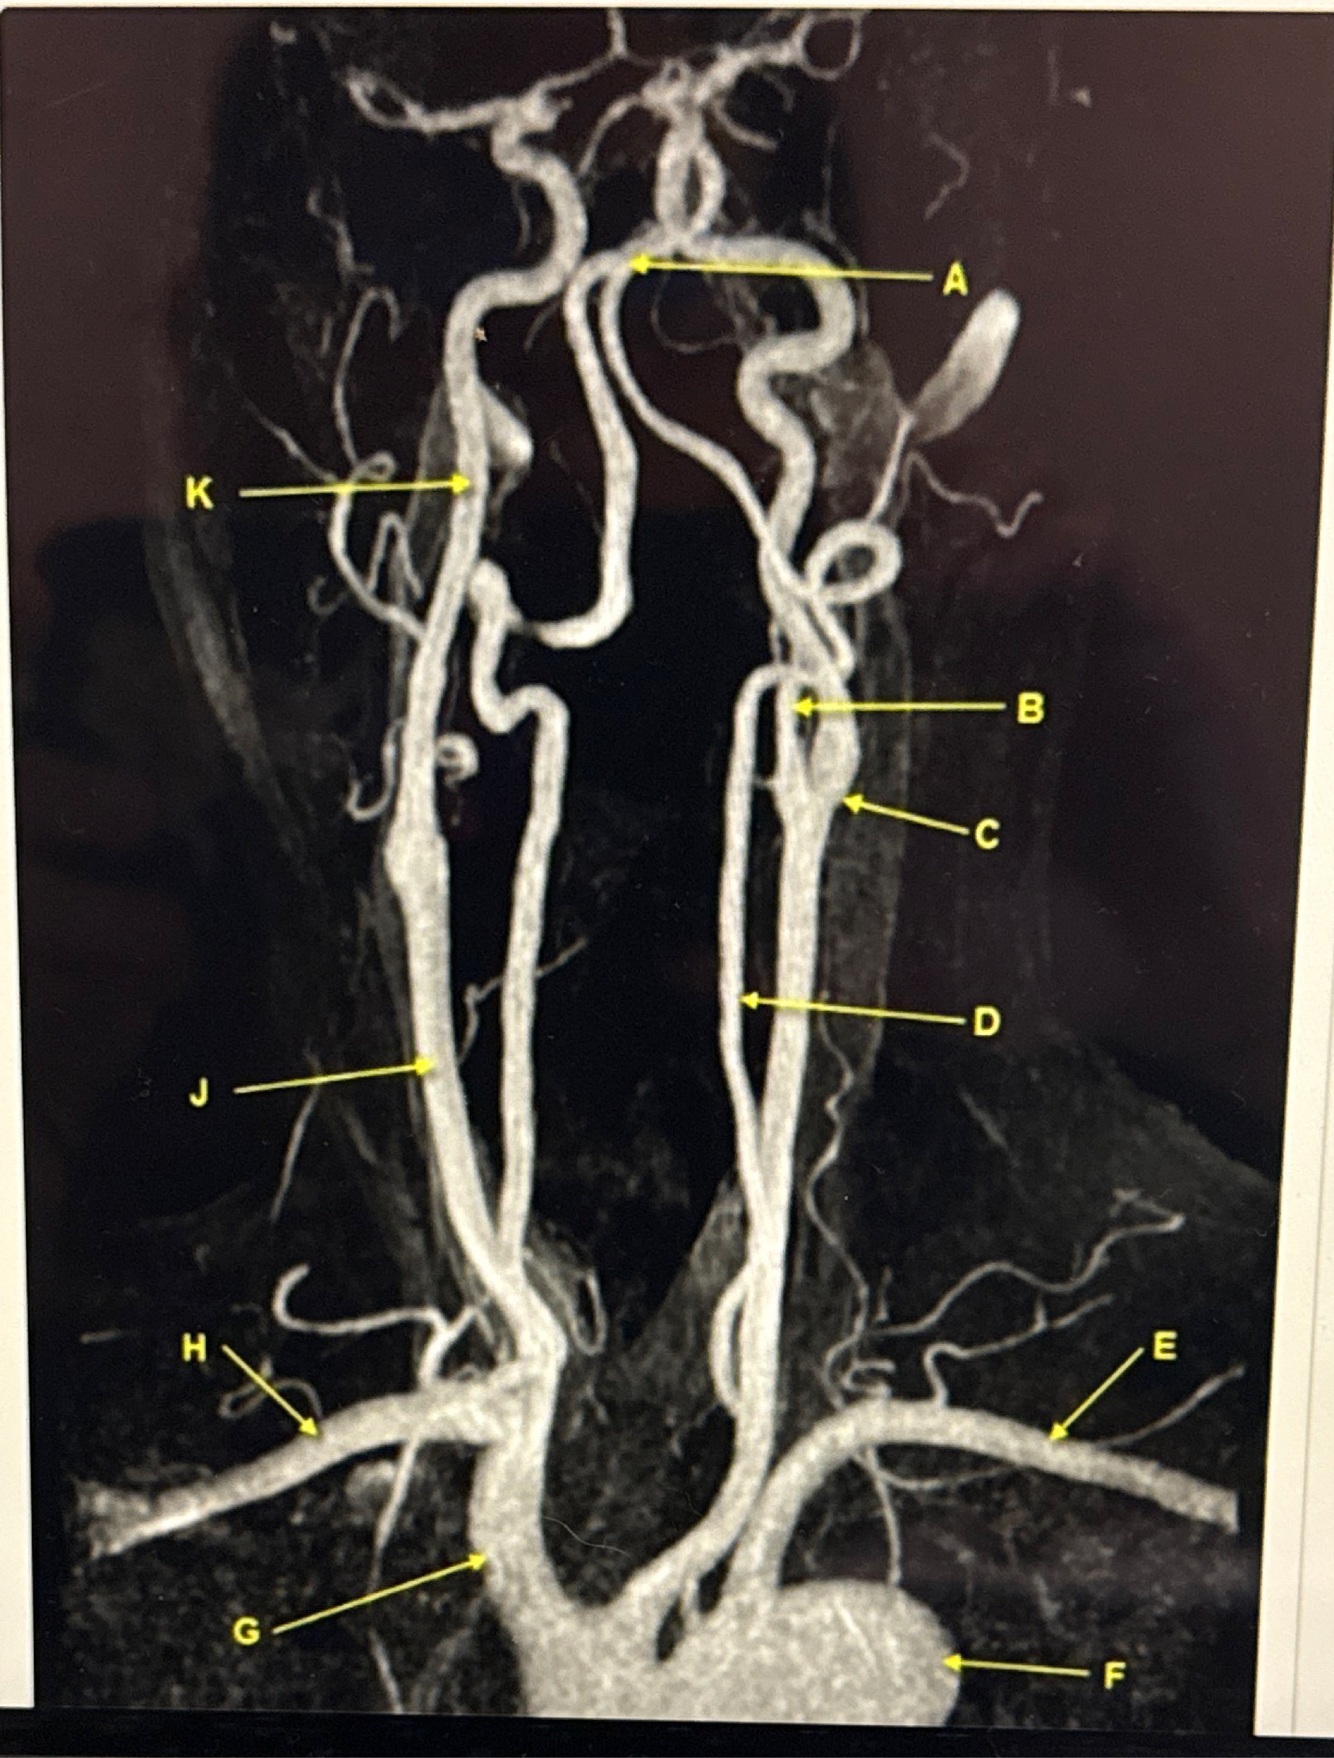

What kind of MR image

MRA EXTRACRANIAL CIRCULATION

Letter B points to

Letter J points to

Letter A points to the

Letter E points to the

Letter K points to the

Letter C points to the

VertebroBasilar junction

Letter B points to the _______ and letter D points to the ______

B. External carotid artery

D. Vertebral artery

Letter E points to the _____ and letter F points to the _____

E. Left subclavian artery

F. Thoracic aorta

Letter G points to the _____ , letter H points to ______ and letter J points to the

G. Brachiocephalic

H. Right subclavian artery

J. Common carotid artery

Letter K points to the ________,

K. Internal carotid artery